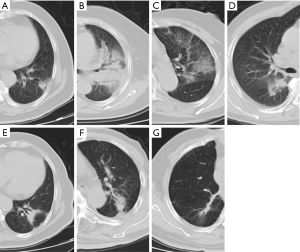

In the follow-up of 7 patients with recurrence, 1 case had no RILI, 2 cases had diffuse consolidation, 4 cases had patchy consolidation and GGO, 3 cases had mass-like pattern, and 3 cases had modified conventional pattern. The characteristics CT changes of patients with recurrence are shown in Table 2. The CT features of acute and late RILI are shown in Figure 1.

The CT characteristics of acute and late RILI are shown in Tables 4 and 5. The Chi-squared test was used to analyze the consistency between the 2 observers on CT characteristics of acute and late RILI, and the Kappa coefficients were 0.706 and 0.72. These showed that the judgement of 2 observers on CT characteristics of acute and late RILI had good consistency. Observer 1 found the patchy consolidation and GGO to be the main CT feature on acute RILI, while observer 2 found patchy GGO to be the main feature. The modified conventional pattern was the main CT feature on late RILI.

Trovo et al. (13) enrolled 68 patients who accepted SBRT and found some patients had acute RILI at 6 weeks after SBRT, most patients had no findings (37, 54.4%), and 11 patients had patchy GGO. In their follow-up, patchy consolidation and GGO was the primary pattern 2–6 months after SBRT, and the modified conventional pattern was the main pattern in late RILI 7–18 months after treatment. The findings are consistent with those of the present study. Hayashi et al. (8) investigated 81 NSCLC patients after SBRT, and 6 patients had tumor relapse, including 5 case of mass-like opacity pattern and 1 case of modified conventional pattern. The present study had 3 cases of mass-like pattern, 3 cases of modified conventional pattern, and 1 case of no injury. That is to say, the mass-like and modified conventional pattern were the main CT patterns of late RILI. We also found that among the 7 patients with relapse of acute RILI, there were 2 cases of diffuse consolidation, 4 cases of patchy consolidation and GGO, and 1 case of no injury. The radiological changes developed in most patients after SBRT, but several researchers have reported slightly different results concerning the main CT pattern. These differences may depend on which delivery technique was chosen, as the frequency and timing of the radiological changes can vary according to the delivery technique (14). Ronden et al. (11) described the typical radiological changes in patients who had undergone SBRT with an older fixed-beam delivery approach, and the most frequent acute radiological changes were diffuse consolidation and patchy consolidation. However, many institutions currently use a modern delivery technique, for which late radiological changes are more common, with the main CT pattern being a modified conventional pattern (62%) that is difficult to distinguish from local recurrence (11,14).